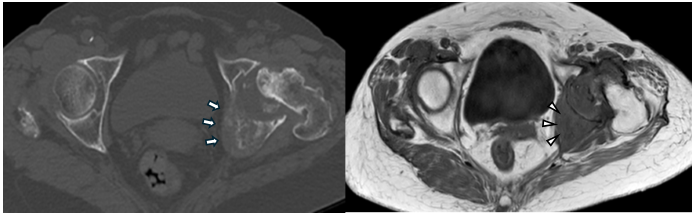

Although she was able sit in a wheelchair, her pain became intolerable. The patient and her family strongly requested surgical intervention for pain relief. Pre-operative computed tomography (CT) and MRI demonstrated metastatic bone destruction involving the left acetabulum and extending toward the ischium (Fig. 4).

Figure 4: Pre-operative computed tomography (CT) (left, axial view) and magnetic resonance imaging (MRI) (right, axial view). The axial CT view shows osteolytic metastatic destruction extending from the acetabulum toward the ischium (arrows). The axial T1-weighted MRI view demonstrates a metastatic lesion involving the superior acetabular dome, corresponding to the weight-bearing region (arrowheads).

Because the degree of acetabular destruction made placement of a cementless cup difficult, THA using the restoration GAP II reinforcement ring and a cemented acetabular cup was planned.